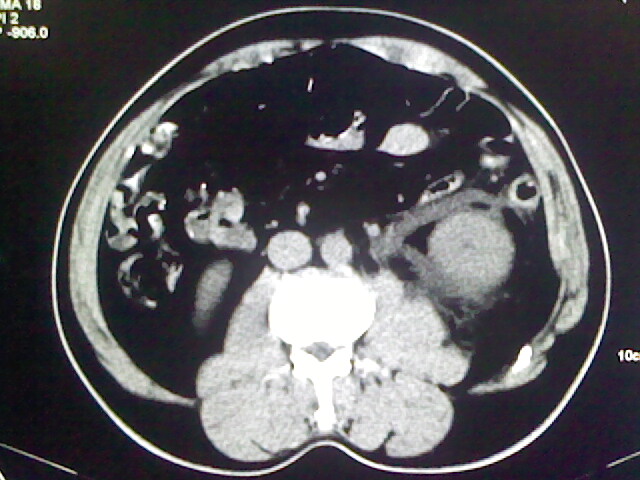

以下是引用zsl6918在2009-2-7 7:29:00的发言:[br]请提供介入的方式方法,肾及输尿管改变考虑与介入损伤有关,漏了,尿液外渗。

以下是引用余辉在2009-2-7 8:27:00的发言:[br]可能是硬化剂烧穿囊壁进入肾盂输尿管了,尿漏。不除外介入或碎石术后合并感染[br]患者术后怀疑结石,接着就碎石了?就怀疑没有确诊吗?碎石用的什么方法?气压弹道还是体外超声?如果这样的话责任人都难找

以下是引用随光逐影在2009-2-7 8:46:00的发言:[br]支持3楼意见。[br]另:不排除左肾及肾周感染可能。